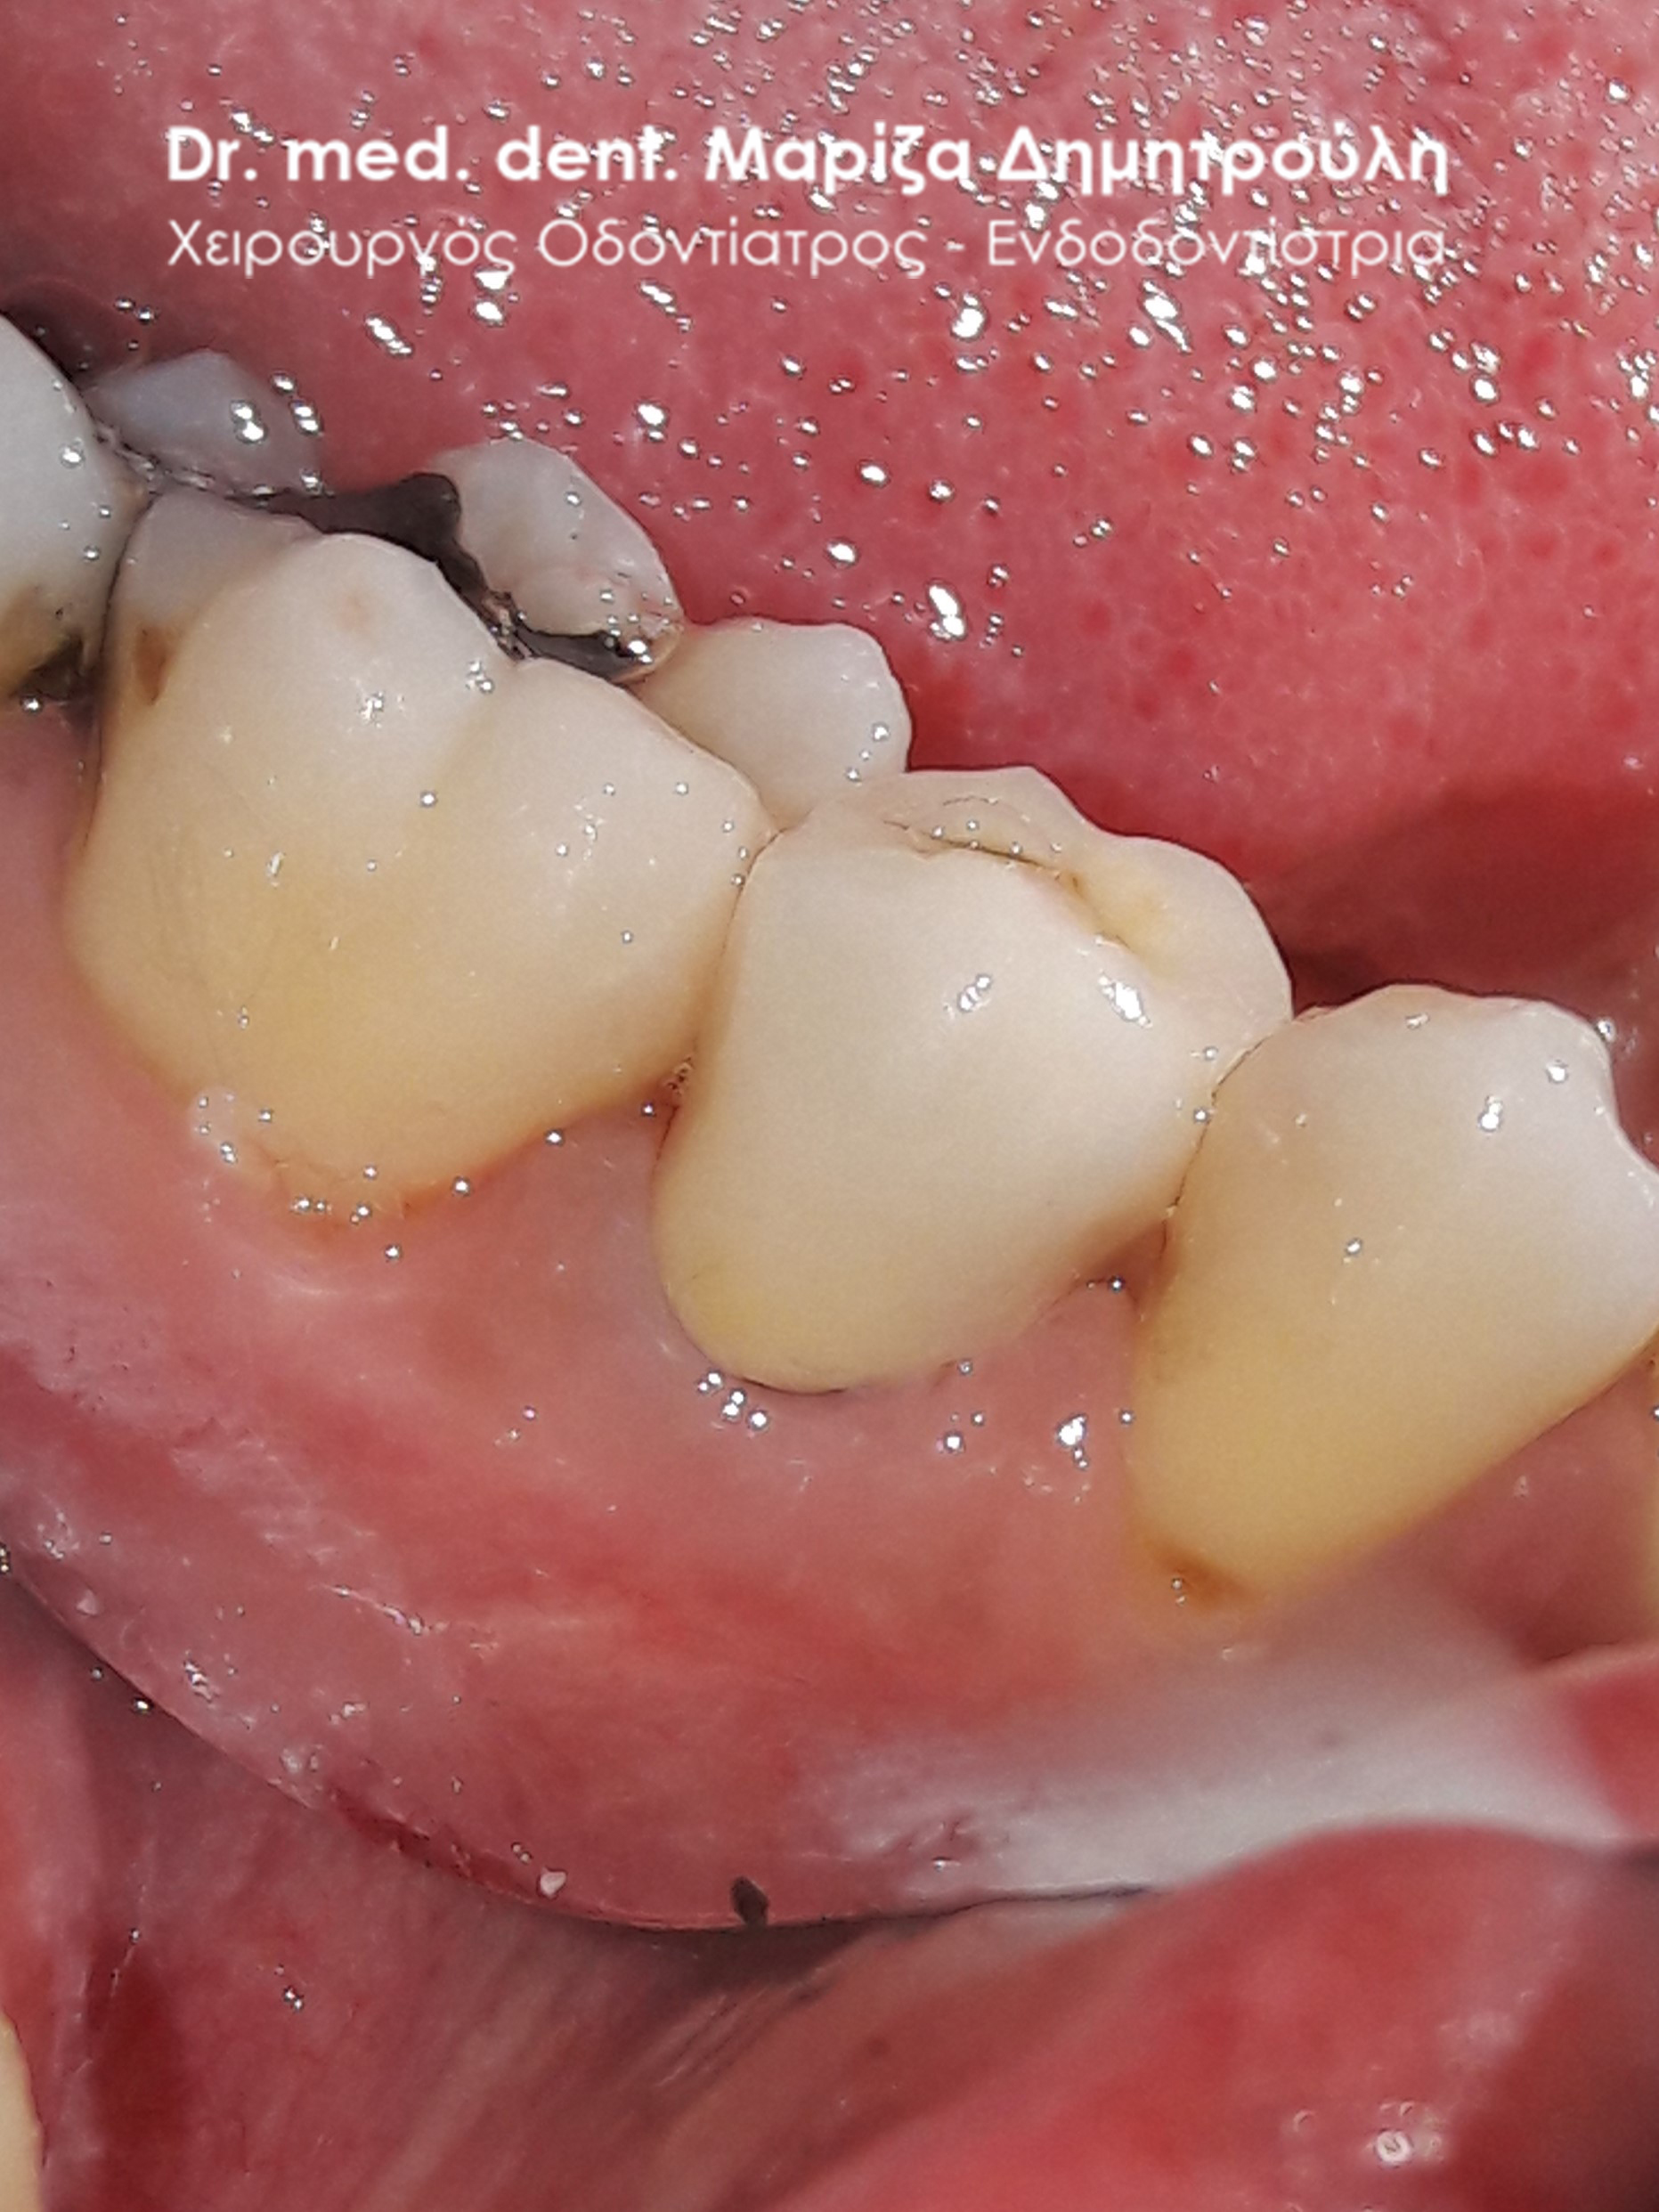

Περιστατικό – Ολοκεραμική στεφάνη / θήκη ζιρκονίου στον άνω αριστερό γομφίο

Η ασθενής επισκέφτηκε το ιατρείο μας γιατί πονούσε στον πρώτο άνω αριστερό γομφίο. Η κλινική και ακτινογραφική εξέταση φανέρωσε την αναγκαιότητα απονεύρωσης του δοντιού. Μετά το πέρας της ενδοδοντικής θεραπείας και εφόσον το οδοντικό έλλειμα ήταν μεγάλο, κρίθηκε απαραίτητη η προστασία του απονευρωμένου δοντιού με ολοκεραμική θήκη.

Αρχική κλινική εικόνα του δοντιού με το προσωρινό σφράγισμα απονεύρωσης